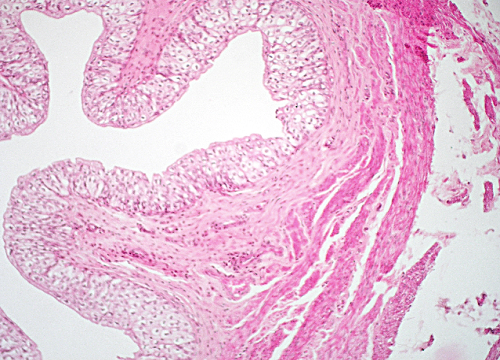

Question 12

Question

Label this image

Image:

c5acbc5f-7ce1-43ce-8881-898cec4f35b1 (image/png)

Answer

Stomach Fundus